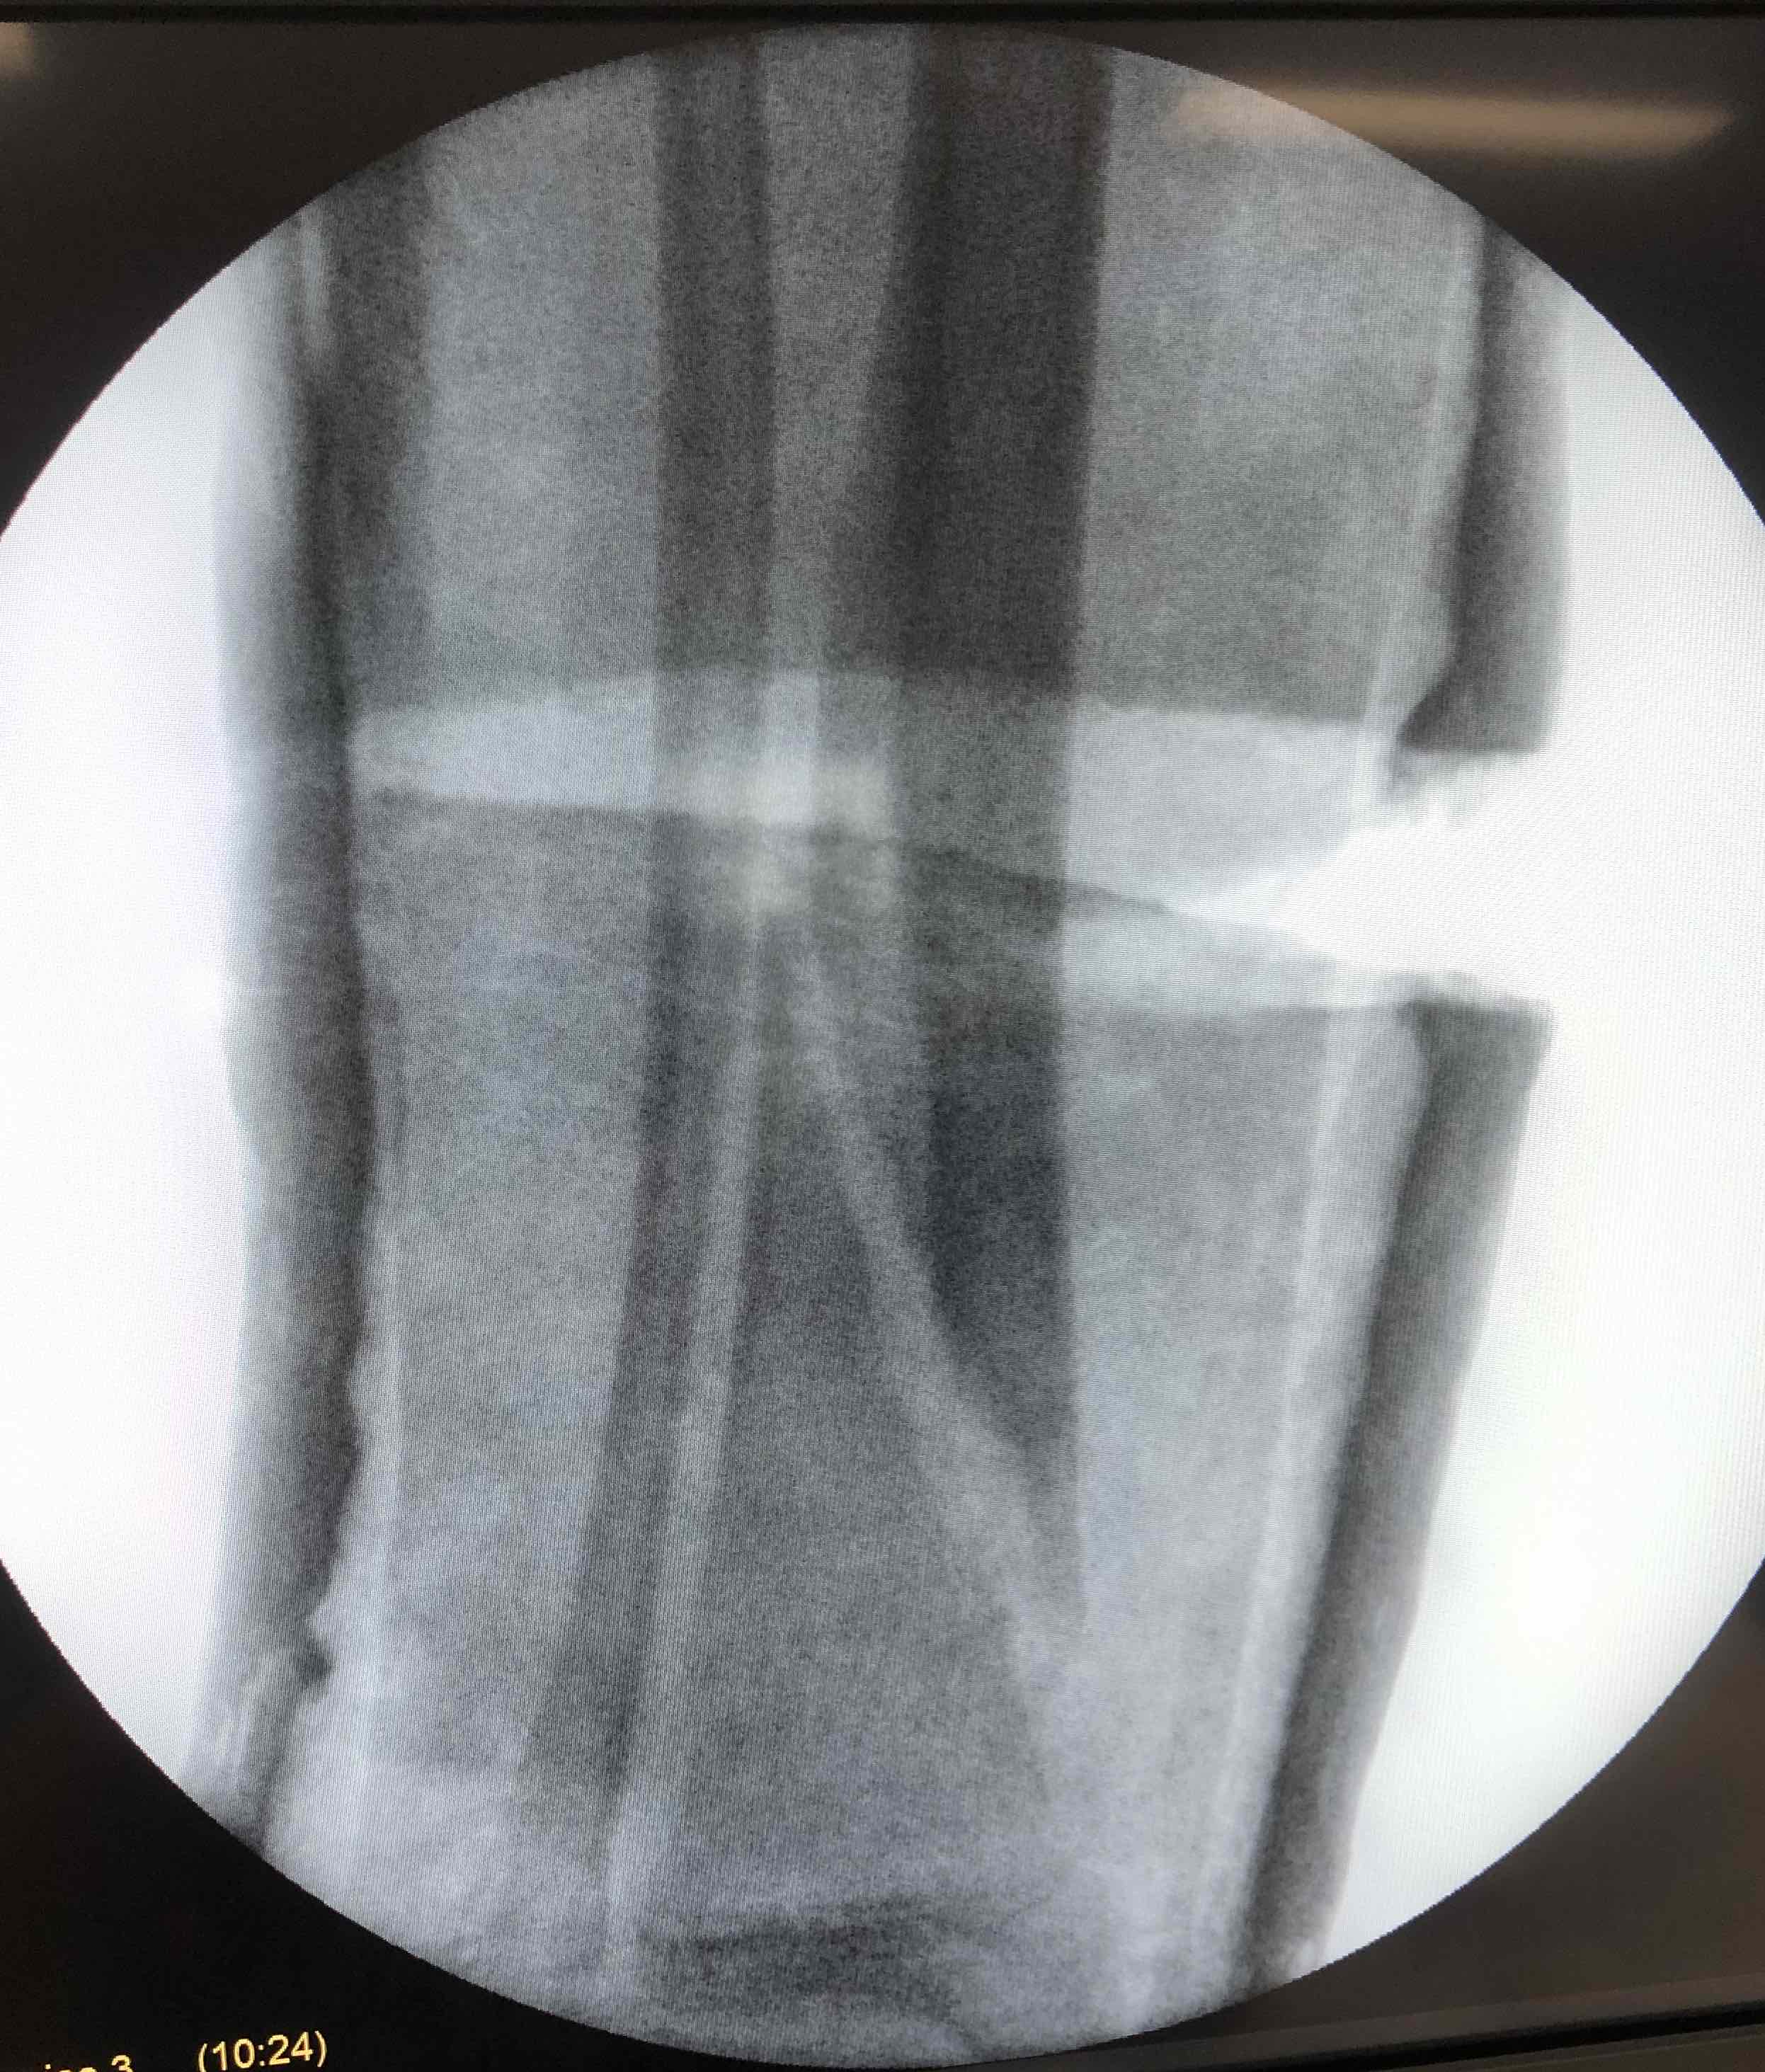

GA / II

- leg hanging over edge of bed

- gravity assists reduction

- apply short leg cast

- check II